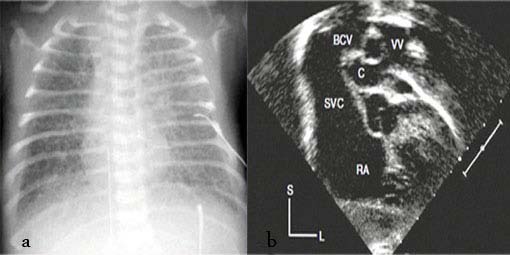

The patient didn't carry any congenital heart disease (CHD) history in his genetically close relatives (first, second and third degree). Immediate and brief work up was carried out. Chest X Ray (CXR) showed normal heart size with ground glass appearance in all the lung fields (fig. 1. a). Color Doppler and 2D-echocardiography revealed the total anomalous pulmonary venous connection (TAPVC -supra cardiac type), accompanied by significant gradient between the drainage point of vertical vein to the left brachiocephalic vein and the pulmonary veins with flow acceleration > 3.0 m/sec (pulmonary venous obstruction). It was also uncovered presence of the ASD secundum, as the natural last resort for being alive. The vertical vein was noted to be compressed as it coursed posterior the left pulmonary artery and anterior the left main bronchus (fig. 1.b). According to the aforementioned findings, the boy had almost met most of incremental risk factors leading to mortality after conventional operations.